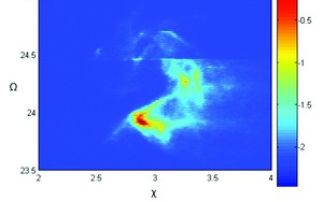

Over the last few years, IR absorption spectroscopy has grown up as a potential analytical method in tissue and cell studies for cancer diagnosis. ...